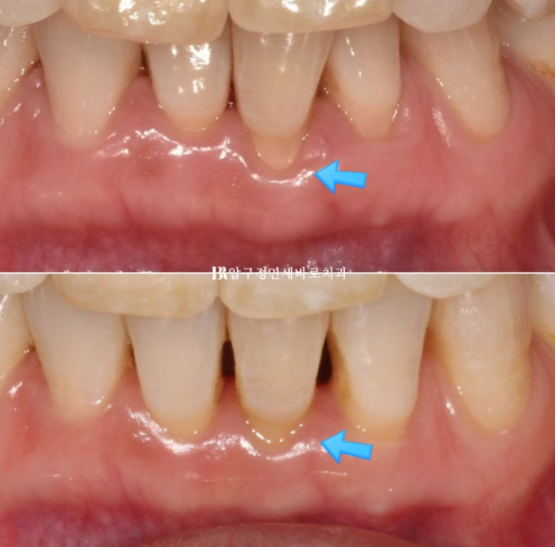

파란 화살표 부분은 잇몸이 주변치아에 비해 내려가있습니다

그 이유는 배열에서 가장 벗어난 치아여서 입니다.

제자리로 넣어주면 잇몸이 회복되기도 합니다.

배열에서 가장 많이 벗어난 덕분에 잇몸이 유독 내려갔던 치아를 자세히 보겠습니다.

23.07~24.05

잇몸 퇴축이 회복이 되어 치아뿌리 노출이 줄었습니다.